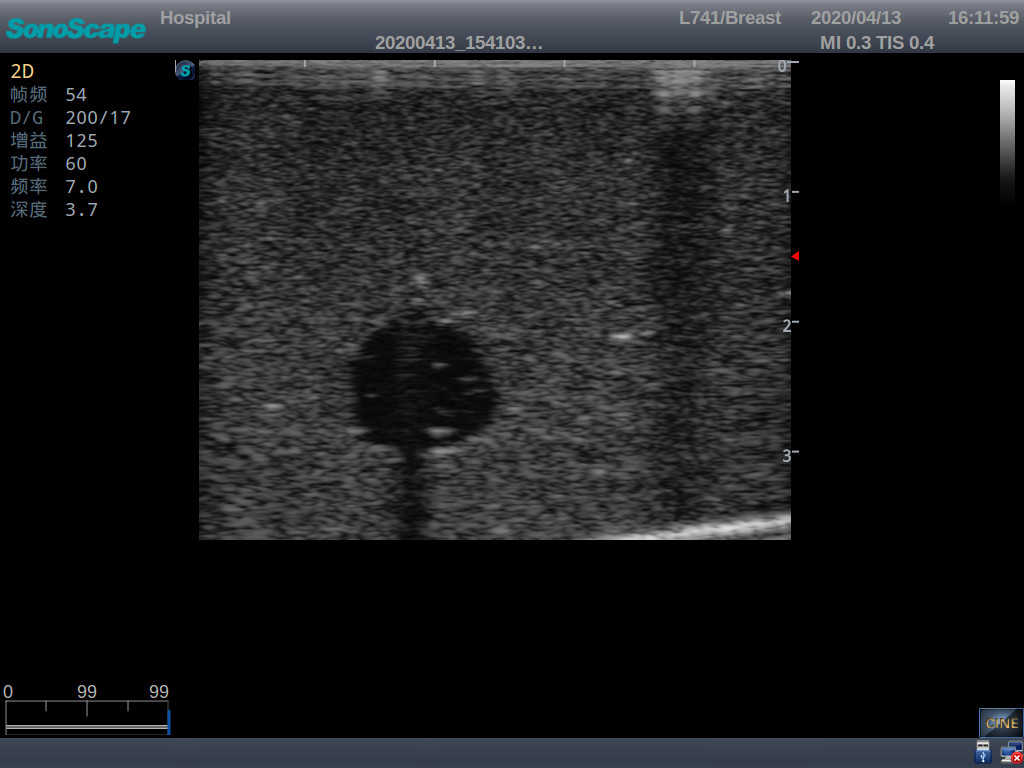

Product size(mm) 908×228×150

2)  Each model contains 8 space-occupying lesions of varying sizes, different in touch, elasticity and ultrasonogram

4) Biomimetic material allowing users to see clear and real normal tissues and space-occupying lesions that are hyperechoic, hypoechoic and isoechoic as they would see in the clinical environment